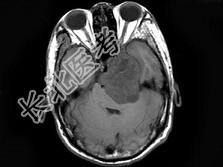

- 单项选择题男,38岁, 左侧面部麻木半年,头颅MRI见颅内占位性病变, 最可能的诊断为 ( )

B、三叉神经瘤